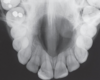

What can be seen in the following image?

A

cementoblastoma